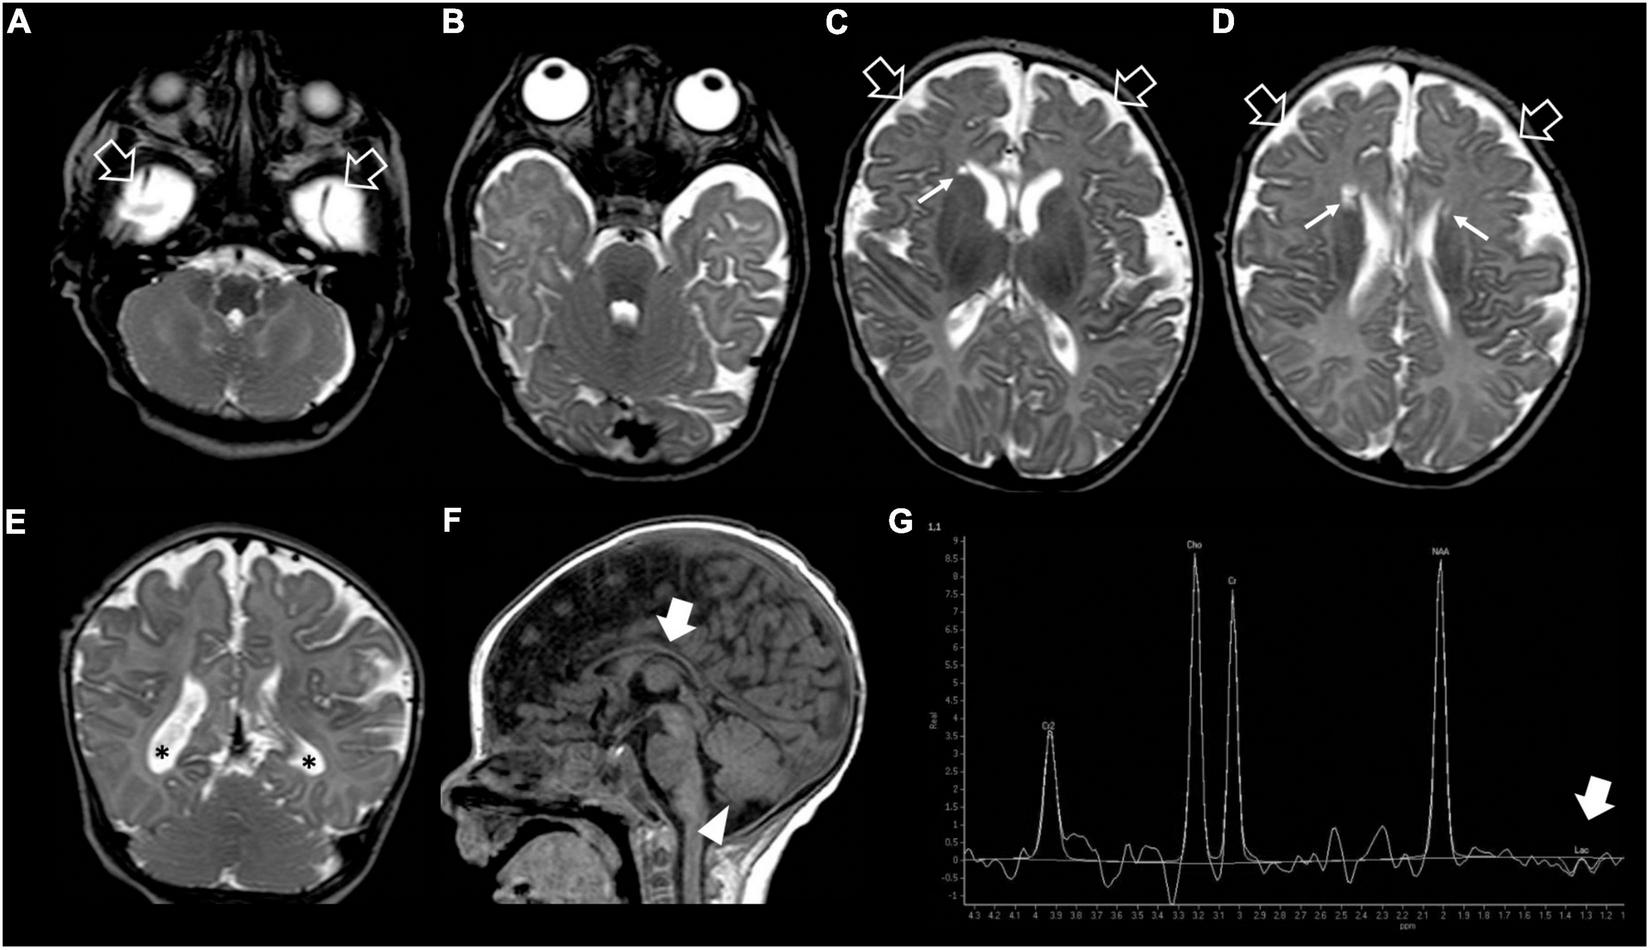

Our patient was the first child of non-consanguineous parents coming from the same small Sicilian area, with unremarkable family history (Figure 1A). The boy was born at 36 weeks of gestation by C-section due to premature rupture of membranes. Birth weight was 3,100 g (90°centile), length 51 cm (97°centile), occipitofrontal circumference (OFC) 33 cm (50°centile), and Apgar score was 8 and 9 at 1 and 5 min. A few hours after birth, he presented hypoglycemia, respiratory distress associated to tonic-clonic seizures, and horizontal nystagmus. The electroencephalography (EEG) showed monomorphic delta activity with epileptiform discharges often accompanied by a sustained rhythmic jerking of the limbs. Brain magnetic resonance imaging (MRI) studies performed at the age of 7 days and 2 months showed frontal bilateral periventricular cysts, enlargement of cerebral subarachnoid spaces, especially in the frontal-temporal regions, and a small inferior vermis. He was evaluated for the first time at our hospital at the age of 4 months. Clinical and neurological evaluation revealed a lack of gaze fixation with horizontal nystagmus, axial hypotonia with spastic hypertonia of the limbs. Dysmorphic features included OFC 41 cm (25°centile), short neck, low anterior hairline, bushy eyebrows, long eyelashes, and broad nasal bridge (Figure 1B). EEG during wakefulness was characterized by slow monomorphic activity and multifocal independent spikes and spikes and waves. He presented multi-daily asymmetric tonic seizures (with eye and head deviation to the left, left arm hyperextension and right arm flexion) corresponding on EEG to a generalized high voltage slow wave with overlap of low amplitude fast activity and generalized voltage attenuation. Brain MRI at 4 months of age revealed delayed myelination, reduction of the white matter volume, and reabsorption of the periventricular cysts (Figure 2). Brain MR spectroscopy showed small lactate peaks. Over the years, the interictal epileptiform anomalies increased and the background activity became more disorganized. Several anti-seizure medications (ASM) were ineffective (i.e., valproate, vigabatrin, clonazepam, clobazam, levetiracetam, rufinamide, and CBD oil) or determined adverse events such as extreme drowsiness or increased secretions (i.e., phenobarbital, nitrazepam). Moreover, three cycles of ACTH had very poor results. The ketogenic diet did not significantly improve seizures and was suspended. Current ASMs include vigabatrin (70 mg/kg/day), clobazam (1 mg/kg/day) and clonazepam (0.9 mg/day). The multi-daily seizures progressed along with a severe movement disorder characterized by spastic tetraparesis and dystonia of limbs and trunk, worsening during periods of distress or discomfort. No developmental milestones were achieved. Brain MRI performed at 2 years and 4 months revealed mild progression of the brain atrophy and marked reduction with signal alterations of the periventricular white matter, especially in the parietal-occipital regions, thinned corpus callosum, and squared lateral ventricles. Mild signal alterations were also noted at the level of the pons and dentate nuclei (Figure 3). Brain MR spectroscopy demonstrated mild NAA reduction and the absence of lactate peaks (Figure 3). At 3 years, gastrostomy was placed due to failure to thrive and severe gastroesophageal reflux. At the last hospitalization, he showed profound intellectual disability, he was unable to follow objects and he never acquired sitting position. His severe spasticity and dystonia responded poorly to pharmacological treatment with baclofen. He developed scoliosis, and airway secretion accumulation required cough machine use. He presented bilateral ascending testis from the second month of life. The multi-daily seizures, up to 50 attacks per day, strongly disturbed his sleep. Specific tests for metabolic disorders (including neurotransmitters, folate, pterins, amino and organic acids, carnitine profile, plasma very long-chain fatty acids) were performed both on cerebrospinal fluid (CSF), blood and urine samples resulting within normal limits. Ophthalmological examination and auditory brain stem response did not show any pathological findings.

FIGURE 2

Brain MRI and MR spectroscopy at 4 months of age. (A–D) Axial and (E) Coronal T2-weighted images reveal delayed myelination, bilateral frontal periventricular cysts (arrows), enlarged subarachnoid spaces especially in the frontal-temporal regions (empty arrows), reduced white matter volume with mild lateral ventricle dilatation (asterisks). (F) Sagittal T1-weighted image shows hypoplasia of the corpus callosum (thick arrow) and inferior cerebellar vermis (arrowhead). (G) Brain MR spectroscopy performed at the level of the right basal ganglia demonstrates small lactate peaks (thick arrow).